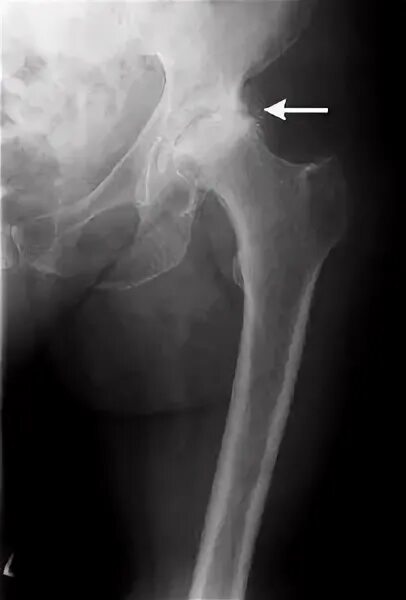

Как лечить коксартроз тазобедренного сустава 1